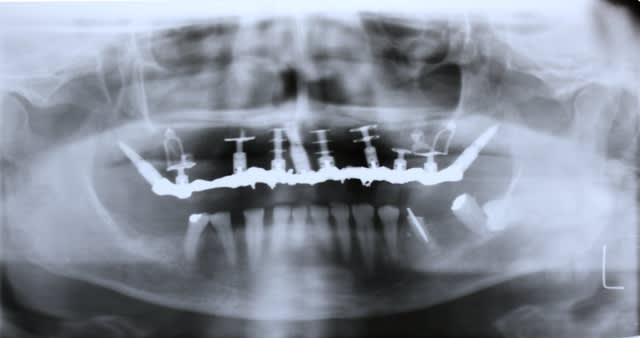

Programmé le 24 sept pour vous faire patienter mieux

Maxillaire complet extraction - implantation

Pas possible de poser que des cylindres voire même très peu voire aucun

Regardez bien les ostéolyses autour des canines

Bref 2 ptérygo, 2 plaques en molaires, deux disk en canine 1 simple et un double, un cylindre ds le trou naso palatin, 2 triple disk en 11 12 et 21 22 et enfin un monodisk en 24...ça a été galère mais c est fait

Pano dispo à partir de samedi